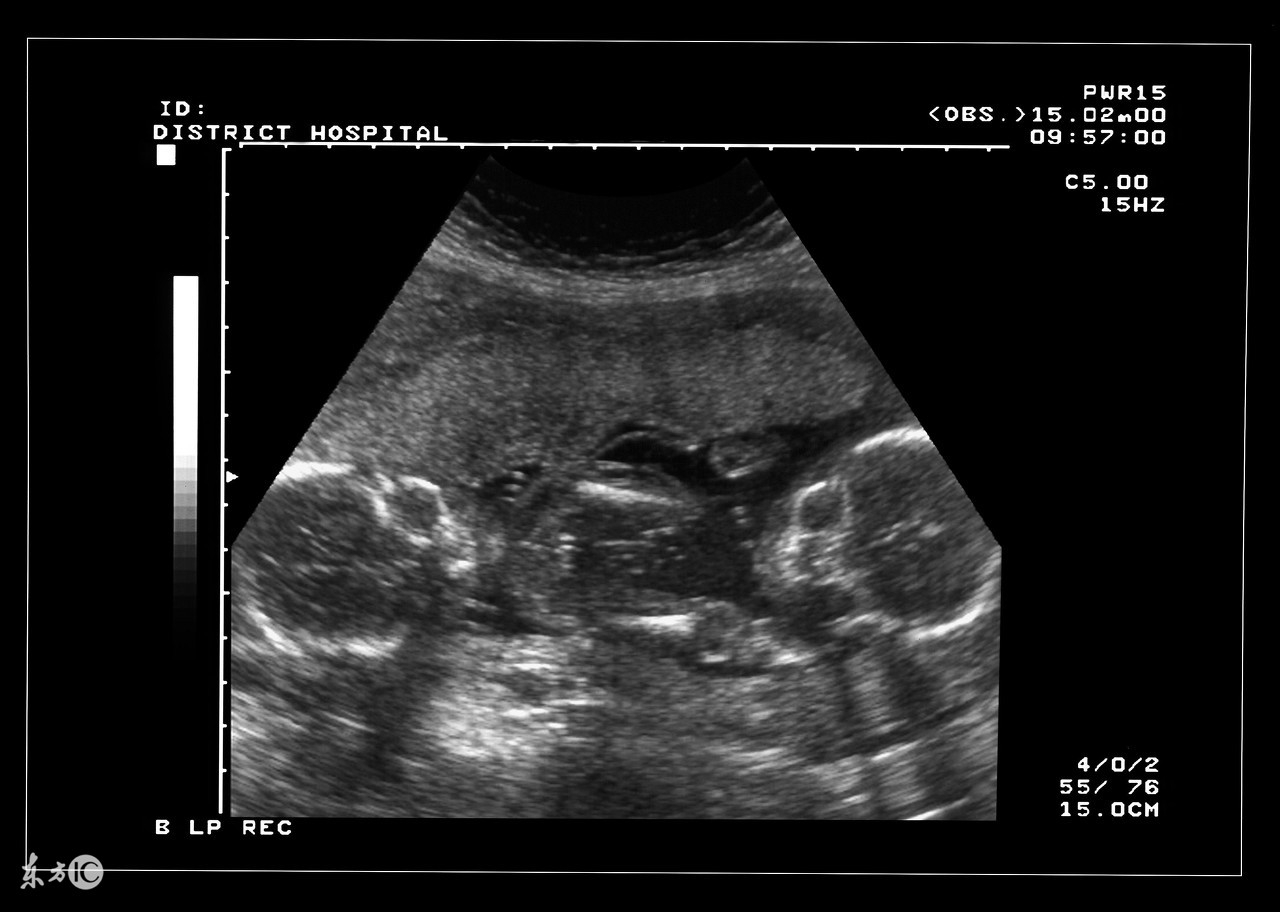

双胎妊娠检查非常重要。由于双胎孕妇比一般孕妇子宫明显增大,这不仅增加了孕妇身体的负担,还由于对其心、肺及下腔静脉的压迫而容易产生心慌、呼吸困难及下肢浮肿等不适。双胎妊娠出现妊娠合并症者也较多,其妊高娠的发生率明显高于一胎妊娠,所以双胎妊娠者要听从医嘱,按期去医院接受检查。

双胎妊娠由于子宫腔相对狭窄胎盘血液循环障碍,其流产发生率较单胎妊娠高2—3倍,因此应加强孕期保护与监护。若一胎发生死胎,另一胎仍可继续生长发育,死亡的胎儿将被吸收或挤压成纸样儿随正常胎儿娩出,不必担心害怕,更不要引产终止妊娠。因双胎妊娠子宫过度膨胀,易发生早产,故应于中期妊娠后关注休息,避免房事,并提前4周做好分娩前的准备工作。由于妊娠的并发症尤其是妊高娠的发生率比较高,从母子安全考虑,应在预产期即住院待产,以免发生早产或其他不测。